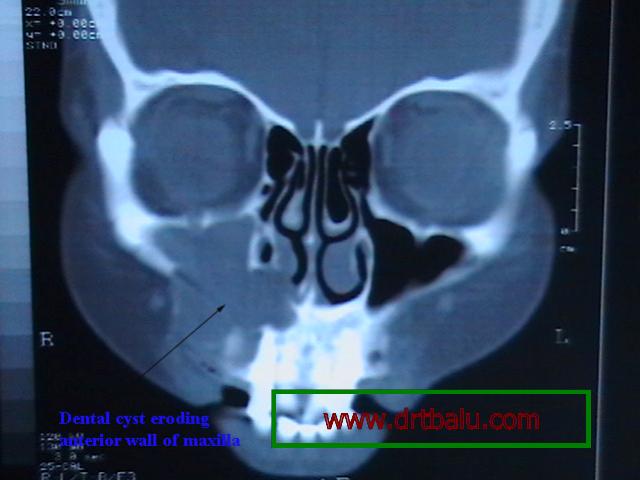

Clinical features: As the cyst expands it causes erosion of the floor of the maxillary sinus. As soon as it enters the maxillary antrum the expansion starts to occur a little faster because there is space available for expansion. When it reaches a size wherein it fills up the whole antrum, it can erode the anterior wall of the maxilla (in the canine fossa area). This is the weakest portion of the maxillay bone. When it erodes the anterior wall of the maxilla it could cause expansion of the maxilla which could be seen as a swelling in the cheek area. On palpation egg shell crackling may be felt in the anterior wall of the maxilla over the canine fossa. There will be associated tenderness.

Coronal CT scan showing Dental cyst of right maxilla